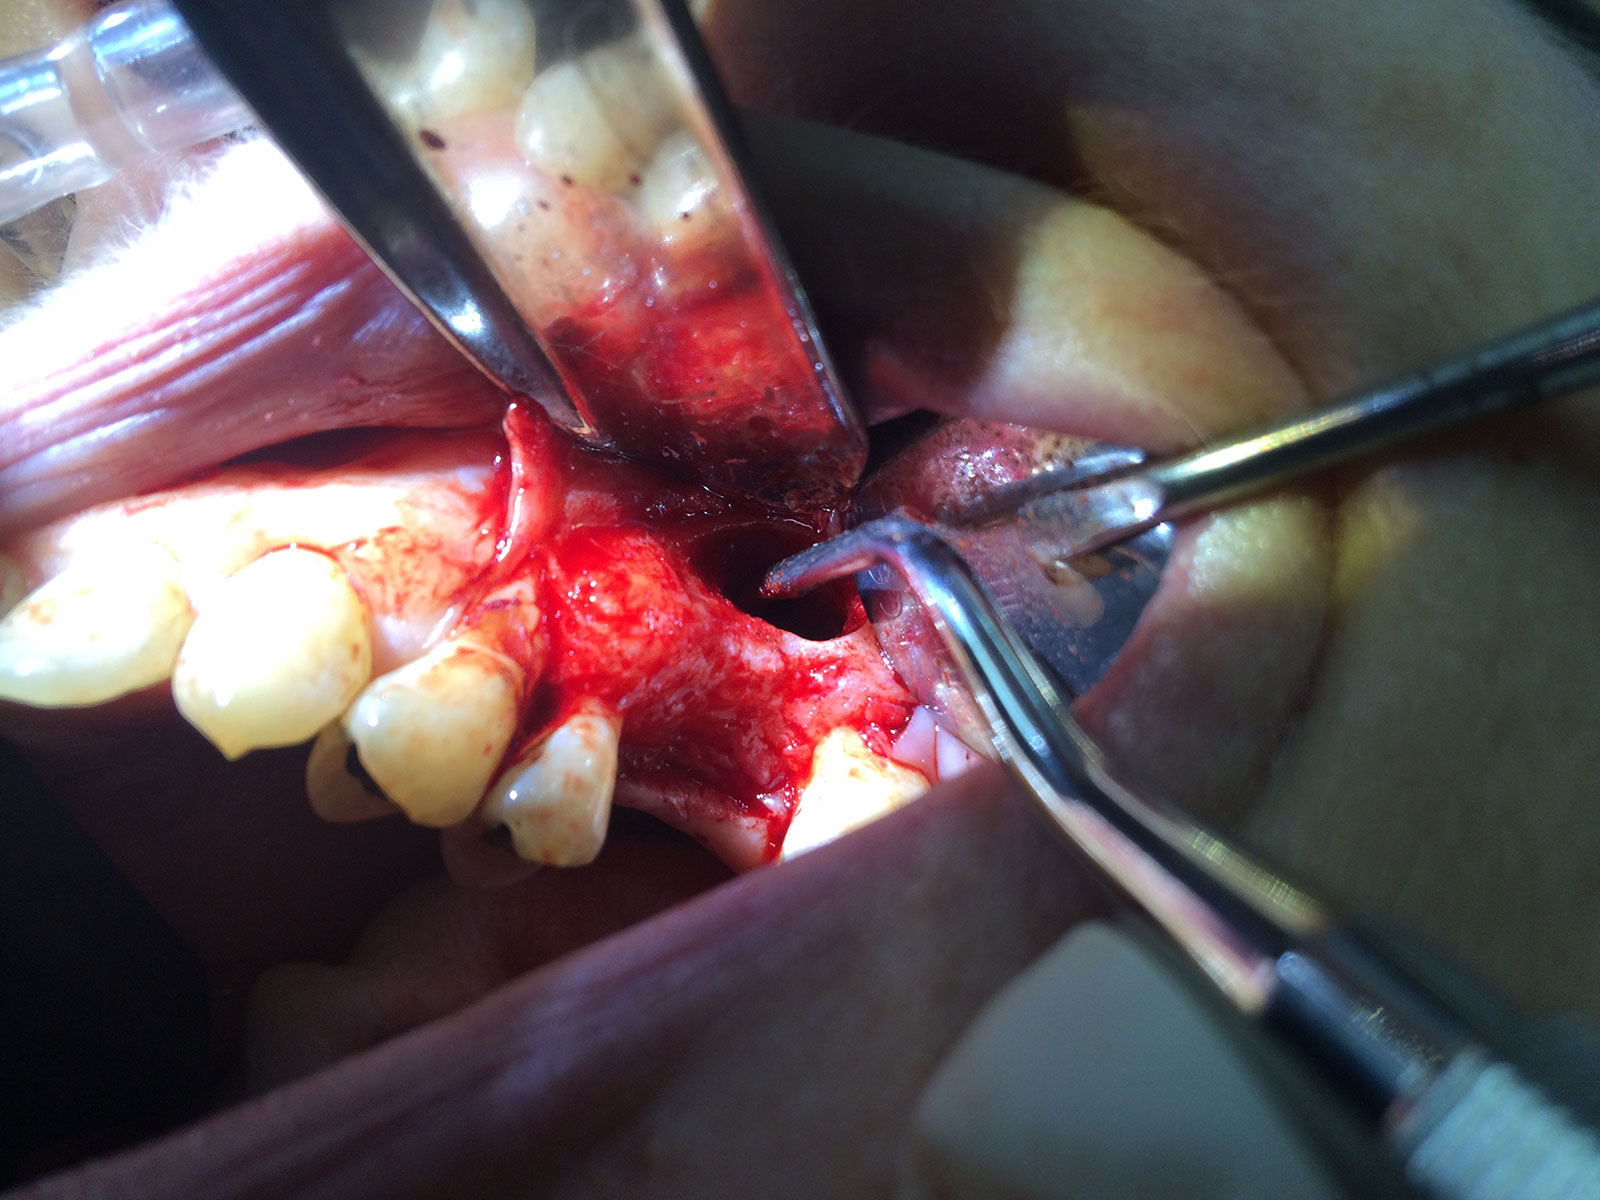

Sinus Grafting Procedures

A sinus grafting procedure, also known as a sinus augmentation, is for patients who have insufficient natural bone in the areas where dental implants are needed. They are long lasting, strong and sturdy, and fit and function like natural teeth. The procedure involves adding bone, either your own natural bone from another part of the body, from a donor or made of processed or synthetic bone material, and placing it below the sinus so that the implants can be placed. After the bone has healed and developed, usually around four to 12 months, the dental implants can be placed.

The photos on this website are from real surgeries performed by Dr. Ulloa. Due to the

graphic nature of the images and content, viewer discretion is advised.

Click to enlarge images